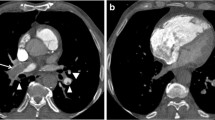

Of the 237 identified patients, 8 (3.3%) were excluded from analysis due to poor technical image quality. In 7 patients (88%), the pulmonary arteries were too poorly enhanced and in one patient, whose CTPA revealed left lower lobe pneumonia, there were too many respiratory artifacts. None of these 8 excluded patients underwent further diagnostic imaging, and they were thus considered negative for VTE. Our analysis included a total of 229 patients with a mean age of 31.7 ± 5.7 years (range 18–49 years), and a mean gestational age of 28 ± 7 weeks (range 6–40 weeks). Among these patients, 16 (7%) had acute PE, 69 (30.1%) had an alternative diagnosis, and 144 (62.9%) exhibited no abnormal findings upon CTPA (Fig. 1). Clinically, pulmonary infection with/without pleural effusion was diagnosed in 17 patients (24.6%), fluid overload with pulmonary opacities (mostly of cardiac, renal, or septic origin) with/without pleural effusion in 21 patients (30.4%), basal atelectasis (mostly due to immobilization or abdominal diseases) with/without pleural effusion in 21 patients (30.4%), pulmonary opacities of another origin (i.e., interstitial lung disease, ARDS) in 8 patients (11.6%), and pleural effusion only in 2 patients (3%). Figures 2 and 3 provide examples of acute PE with associated pulmonary infarction and pulmonary consolidation, thus pulmonary infection, in pregnant patients.

Axial computed tomography pulmonary angiography images in the soft tissue (a) and lung windows (b), from a 25-year-old pregnant patient presenting with acute chest pain. A segmental pulmonary embolus was detected in the left lower lobe (a, white arrow), with associated triangular-shaped areas of subpleural alveolar density (b, arrowheads), consistent with pulmonary infarction

Axial computed tomography pulmonary angiography images in the lung (a) and the soft tissue windows (b), from a 33-year-old pregnant patient presenting with acute chest pain and dyspnea. No pulmonary emboli were detected; however, the scan revealed left lower lobe consolidation consistent with pulmonary infection (a, black arrows)